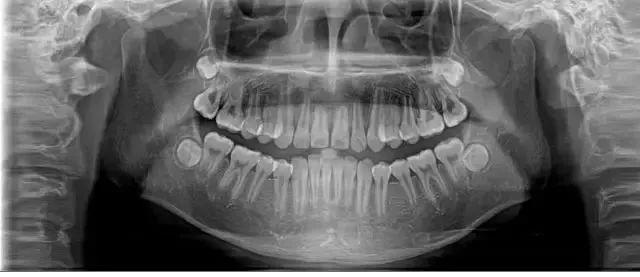

然而以下三个案例都是20多岁的年轻人出现因为严重的牙齿疾病而掉牙的现象。

日前, 25岁的李女士因为牙齿松动、牙龈出血前来郑州大学第一附属医院河南省口腔医院就诊。

医生经过系统检查后,确定这位年轻人出现全口多处牙齿的松动,诊断为侵袭性牙周炎。

主治医生表示,李女士需要进行系统的牙周炎治疗,如果再置之不理会很危险,“最终所有松动的牙齿将会脱落”。而经过系统的治疗后,李女士的牙龈炎症恢复得很快。

有媒体报道,厦门一位26岁年轻女生,牙齿开始松动,最后连肉都咬不动。

经过口腔医院诊断,她患上了严重的牙周炎,医生先后为其拔除了11颗牙齿,并种植了10颗牙齿。

28岁的小孟因刷牙时突然一颗门牙脱落,当她到医院就诊时,医生告诉她上排牙已全部不能保留。

小孟的牙齿已经出现了不同程度的松动,而导致她松动至功能丧失的是严重的牙周炎。最终只能将其牙拔去后,花费十五六万元选择种植牙。

河南省口腔医院牙体牙髓科主治医师汤俊岭表示,在临床中遇见以上类似的情况还是很多的,牙周炎是由牙菌斑中的微生物所引起的牙周支持组织的慢性感染性疾病。

一旦出现牙周炎,会导致牙周支持组织的炎症、牙周袋形成、进行性附着丧失和牙槽骨吸收,最后严重的情况下会导致牙齿松动而被移除。

牙周炎是成年人丧失牙齿的首要原因。

汤俊岭介绍,牙周炎分为慢性牙周炎和侵蚀性牙周炎。年轻人掉牙的上述案例就是属于侵蚀性牙周炎,多发生在20~30岁之间的患者中。